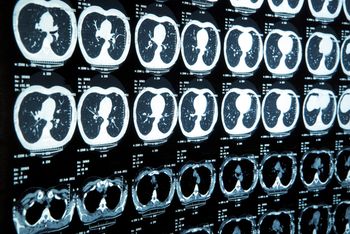

A 73-year-old male with history of a lung mass on recent chest radiograph presents with headaches.